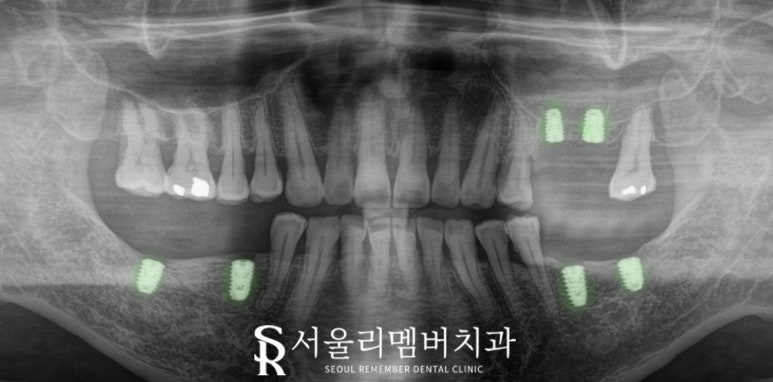

그래서 오신 김에 당일 즉시 식립을 진행하고,

필요에 따라 1주일 뒤 실밥 제거를 하러

한 번만 더 오시면

한동안은 병원에 오실 일이 없도록 합니다.